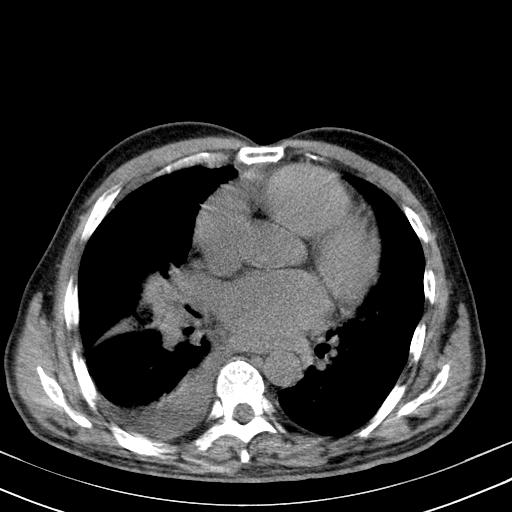

以下是引用zjzjr在2010-3-21 17:39:00的发言:[br]右下中心型肺癌并阻塞性肺炎/不张,纵膈淋巴结肿大,右侧大量胸腔积液,左侧少量胸腔积液

以下是引用zxl51642在2010-3-21 17:06:00的发言:[br]右下中心型肺癌并阻塞性肺炎/不张,纵膈淋巴结肿大,右侧大量胸腔积液,左侧少量胸腔积液,少量腹水。建议纤维支气管镜进一步检查。